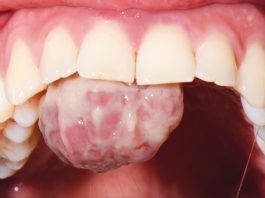

Trattamento chirurgico di un granuloma piogenico in gravidanza

Con il termine granuloma piogenico (GP) si intende una proliferazione tissutale in eccesso provocata da uno stimolo irritativo noto (1). Il principale fattore eziologico...